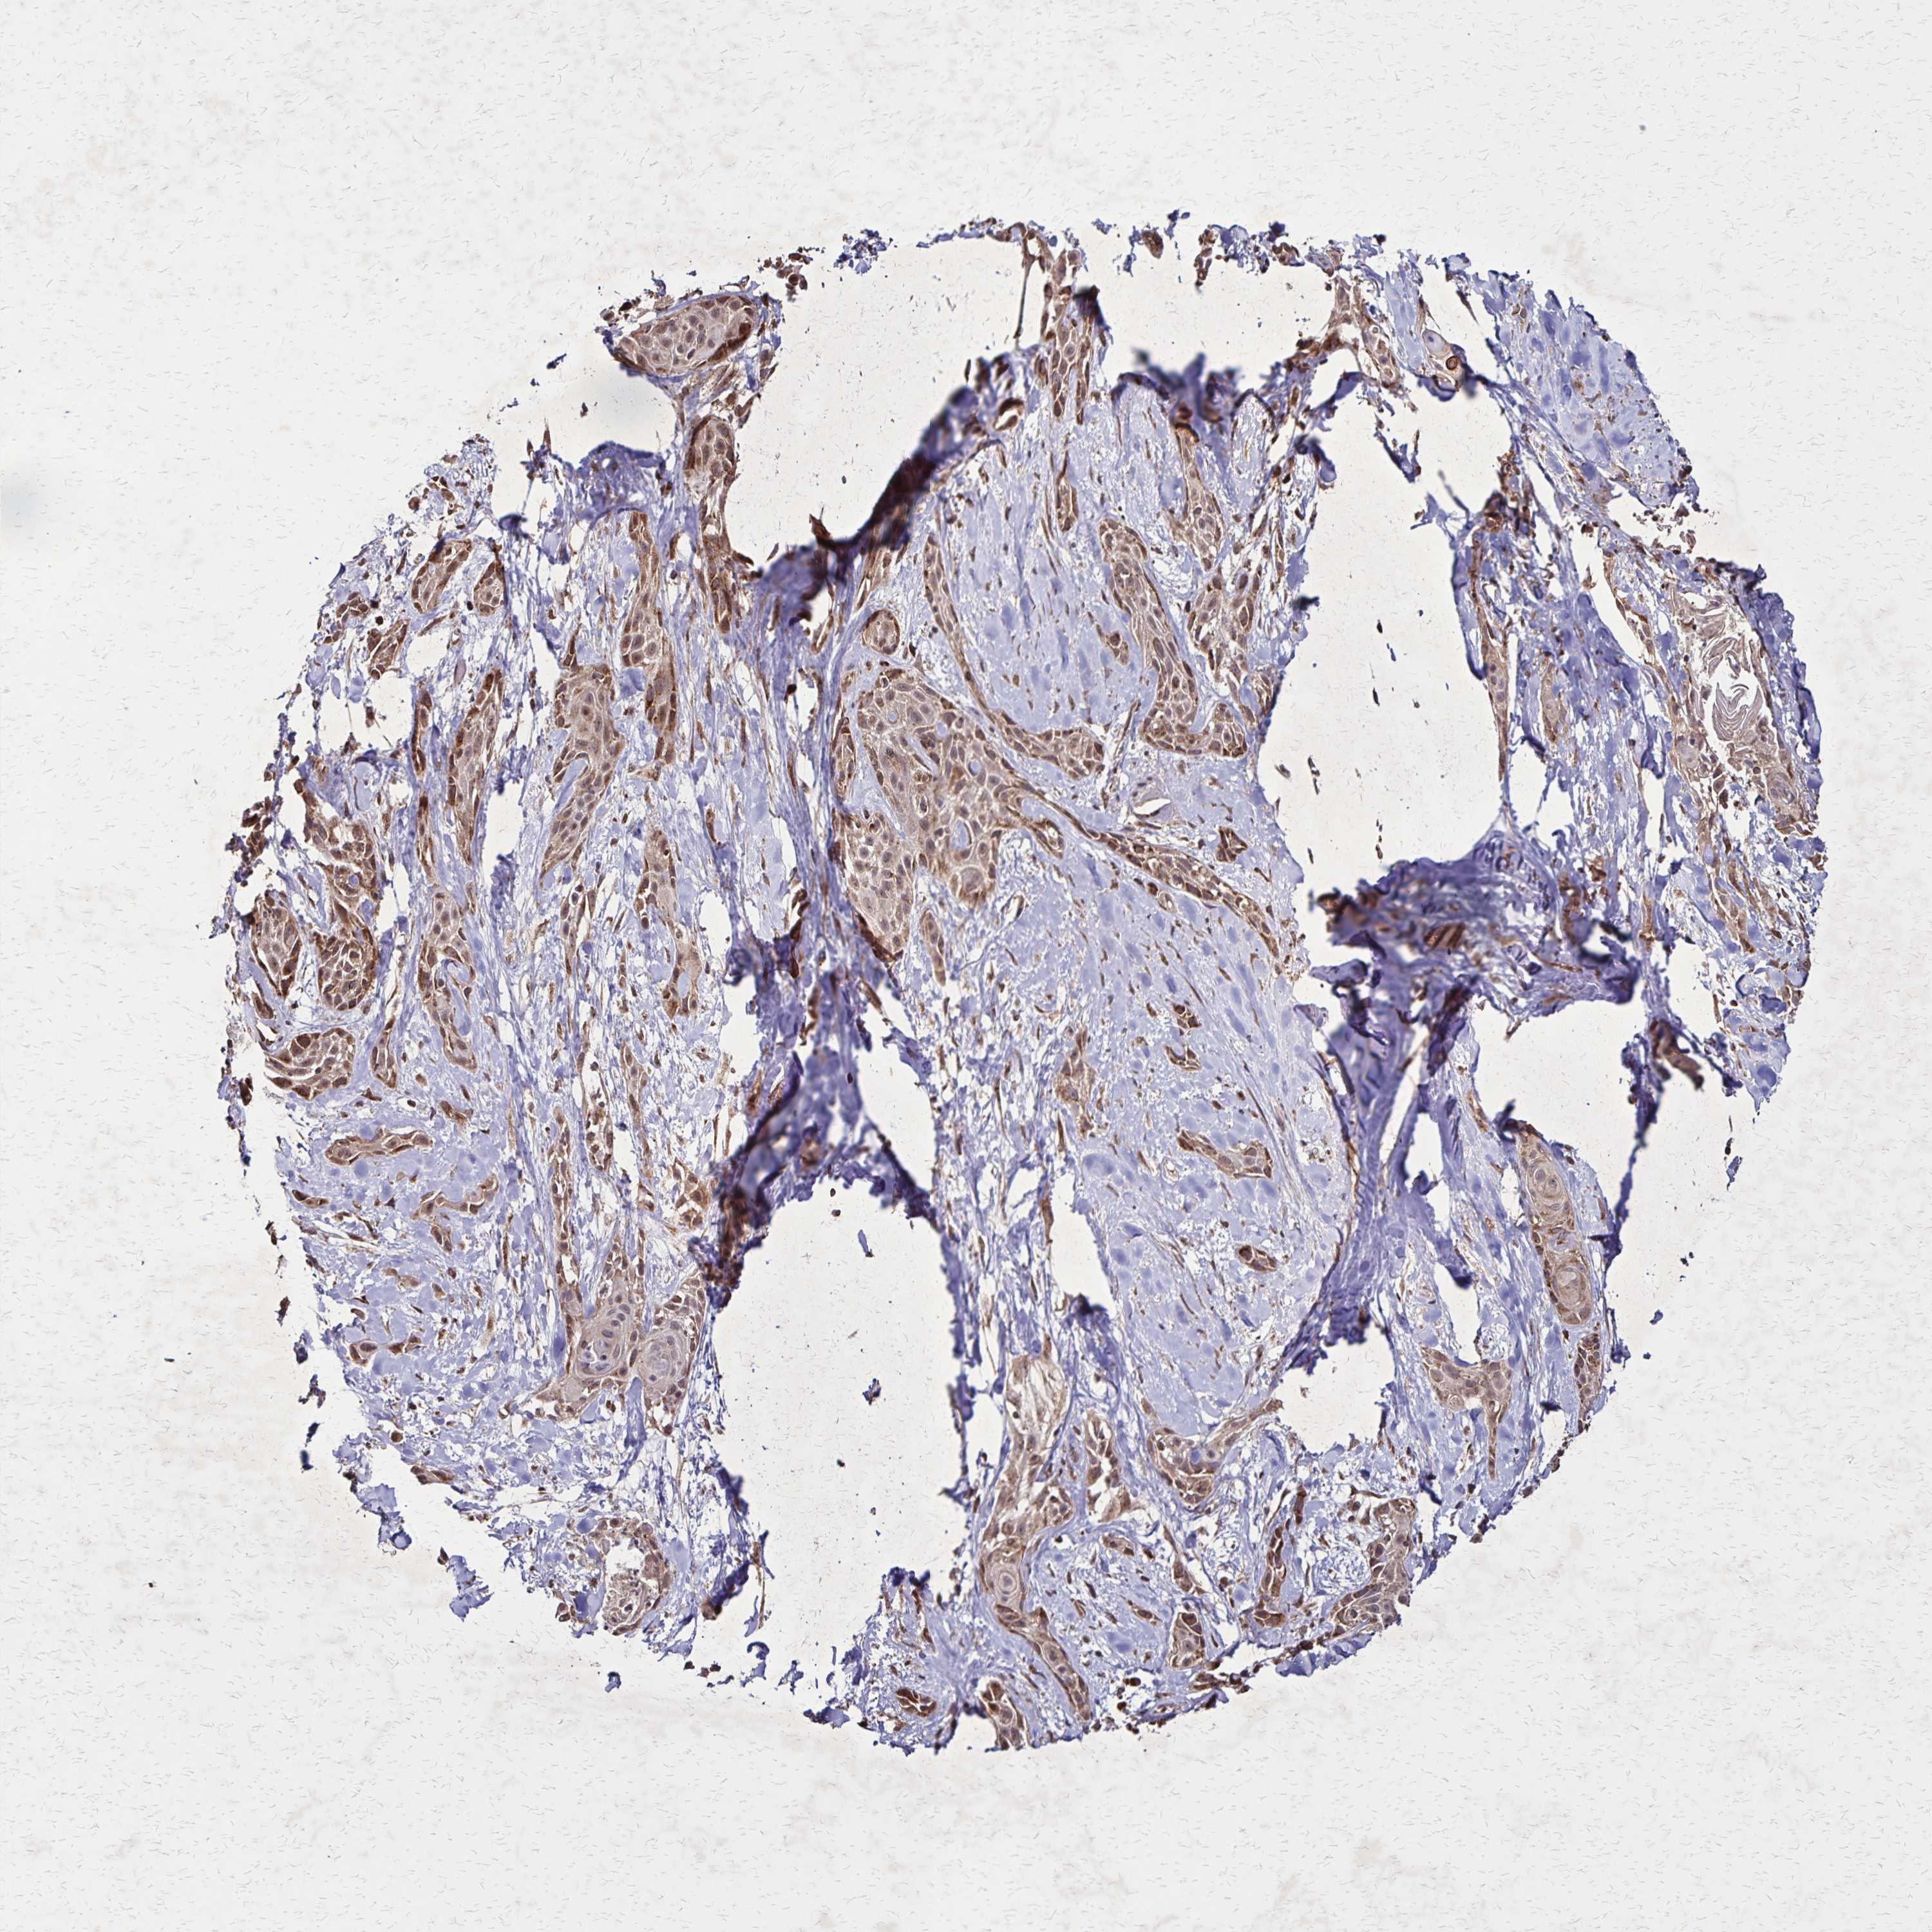

SKIN CANCER - Protein expressioni

A mouse-over function shows sample information and annotation data. Click on an image to view it in a full screen mode. Samples can be filtered based on level of antibody staining by selecting one or several of the following categories: high, medium, low and not detected. The assay and annotation is described here.

Antibody staining in the annotated cell types in the current human tissue is reported as not detected, low, medium, or high, based on conventional immunohistochemistry profiling in selected tissues. This score is based on the combination of the staining intensity and fraction of stained cells.

Each image is clickable and will lead to virtual microscopy that enables deeper exploration of all samples and also displays staining intensity scores, fraction scores and subcellular localization as well as patient and tissue information for each sample.

Antibody HPA051801

Antibody HPA054755

Antibody CAB034314

Basal cell carcinoma

Squamous cell carcinoma, NOS

Squamous cell carcinoma, metastatic, NOS